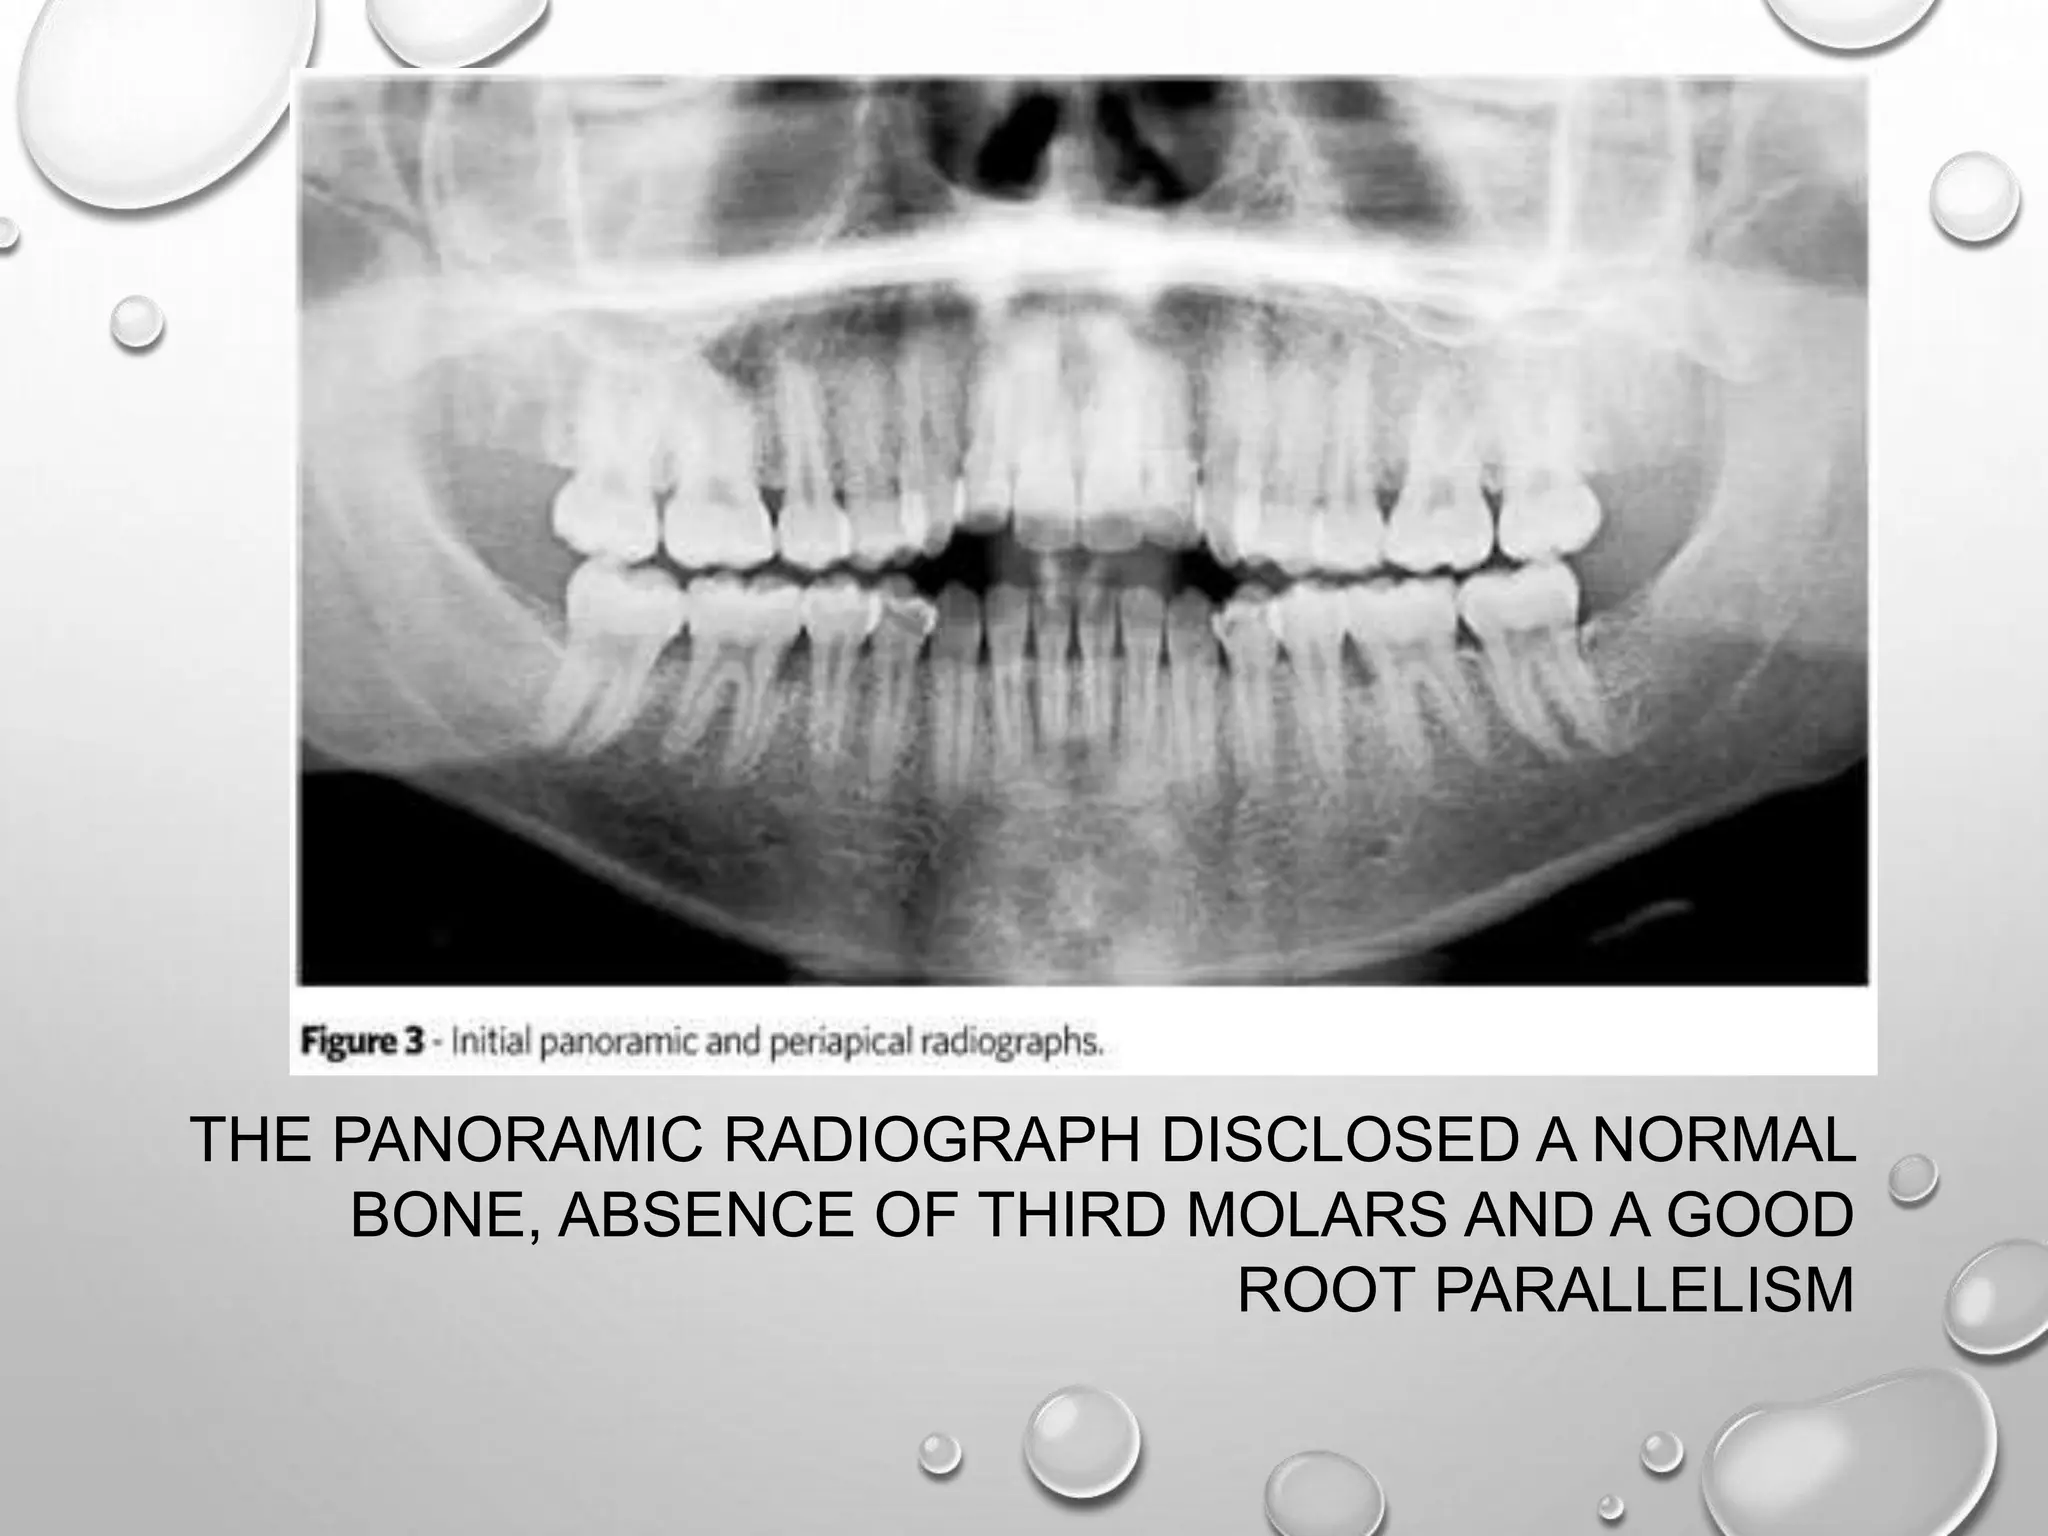

THE PANORAMIC RADIOGRAPH DISCLOSED A NORMAL

BONE, ABSENCE OF THIRD MOLARS AND A GOOD

ROOT PARALLELISM